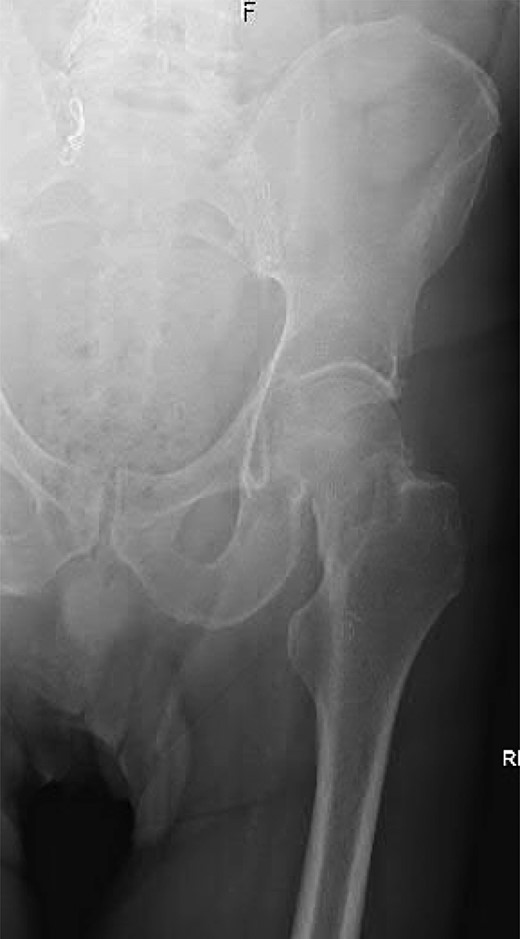

A 74-year-old male was admitted with an intracapsular fractured left neck of femur (Fig. 1). According to the NICE guidelines, he received a cemented THR (Fig. 2) via the posterior approach in the lateral decubitus position. Five weeks prior, he had an EVAR for a leaking AAA. Due to a calcified, narrow right common iliac artery (CIA), the EVAR consisted of a left aortouniiliac endograft with coil embolization of the right CIA and a femoro-femoral crossover graft (Figs 3 and 4).

AP radiograph of the lumbar spine demonstrating the aortouniiliac EVAR with coil embolization of the right CIA.